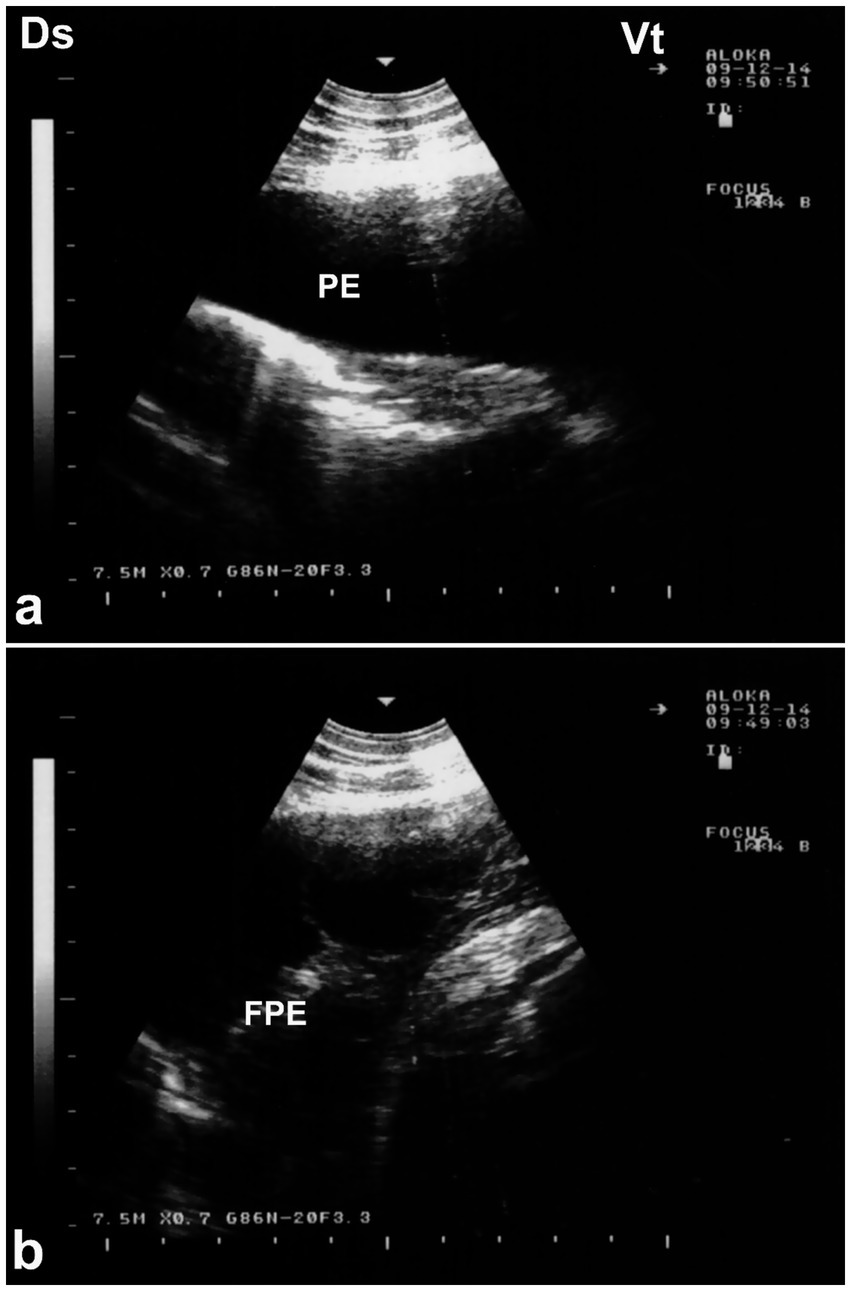

Ultrasonography is considered the most reliable and practical tool for diagnosing pleural effusion in camels, particularly in the absence of accessible radiographic facilities. Sonographic findings typically include an anechoic or hypoechoic fluid accumulation between the visceral and parietal pleura, with displacement or compression of adjacent lung tissue. Fibrin strands, septations, and floating echogenic debris may also be visualized, particularly in exudative or chronic effusions (8). Ultrasonography not only enables accurate assessment of the volume and nature of pleural fluid but also guides safe and effective thoracocentesis, fluid sampling, or drainage procedures. Furthermore, it facilitates serial monitoring of disease progression and response to therapy, thereby enhancing clinical decision-making and prognosis (32). In dromedaries presenting with clinical signs of pleural effusion, ultrasonographic examination reveals hypoechoic to anechoic fluid within the pleural cavity, located between the parietal pleura, diaphragm, and lung. Echogenic strands or fibrin may be visible within this fluid. The accumulation of pleural fluid causes compression atelectasis, particularly in the cranial lung lobes, which appear hypoechoic. Entrapped air in larger bronchi appears hyperechoic and is often accompanied by comet-tail artifacts. Fibrin is visualized as thin, filamentous strands floating within the effusion, loosely attached to the pleural surfaces. It is also common to observe fluid pockets separated by fibrin strands (32) (Figure 12).

Figure 12. Ultrasonographic evidence of pleural effusion in a dromedary camel calf. (a) Longitudinal ultrasonographic image of the right hemithorax showing an anechoic pleural space between the collapsed lung surface and the thoracic wall, consistent with a free, transudative pleural effusion (PE). The underlying lung is partially visualized as a compressed, hypoechoic structure. (b) Left thoracic ultrasound image demonstrating fibrinous pleural effusion (FPE), characterized by multiple echogenic fibrin strands floating within the anechoic fluid. These suspended echogenic bands are indicative of an exudative or inflammatory process, typically associated with infectious pleuropneumonia. Ds – Dorsal; Vt – Ventral [modified from Tharwat (32)].